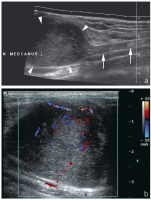

Abbildung 3a-c: (a) Sonographischer Längsschnitt durch den Nervus medianus (Pfeile) am distalen Unterarm eines Patienten mit Karpaltunnelsyndrom: Abrupter Kalibersprung (Pfeilspitzen) im Verlauf unter dem Ligamentum carpi transversum. (b) Sonographischer Querschnitt durch den Nervus medianus bei einem weiteren Patienten mit Karpaltunnelsyndrom: Deutliche Auftreibung des Nervs im proximalen Verlauf unter dem Ligamentum carpi transversum (Pfeilspitzen) mit einer Querschnittsfläche von 0,21 cm2 (Normwert bis 12 cm2). (c) Sonographischer Längsschnitt (selber Patient) durch den aufgetriebenen Nervus medianus (Pfeilspitzen) mit Darstellung multipler Farbsignale, hinweisend auf eine reaktive Entzündung.

Abbildung 4: Sonographischer Querschnitt durch den Karpaltunnel einer Patientin mit klinischem Verdacht auf ein Karpaltunnelsyndrom. Der Nerv weist eine grenzwertige Querschnittsfläche von 0,11 cm2 auf, allerdings zeigt sich bei Hyperextension ein weit unter das Ligamentum carpi transversum (Pfeilspitzen) reichender Muskelbauch (M).* : normale Beugesehne.